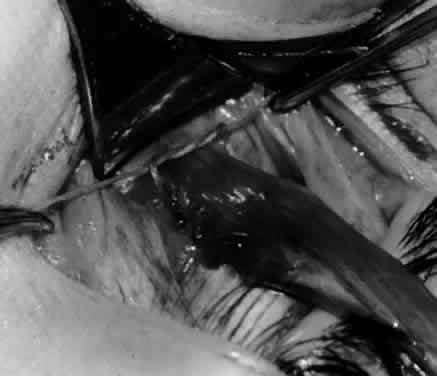

Fig. 9. A Westcott scissor is used to dissect the intermuscular septum and expose the insertion of the inferior oblique muscle.

Fig. 10. The inferior oblique muscle is placed on the Green muscle hook. The exposed insertion is ready for myotomy, myectomy, disinsertion, placement of sutures for recession, or removal for the extirpation procedure.

Fig. 11. Sutures are placed into the insertion of the inferior oblique muscle before it is sectioned from the globe for the recession procedure.

Fig. 12. An Aebli scissor is placed beneath the inferior oblique muscle insertion before it is sectioned from the globe.